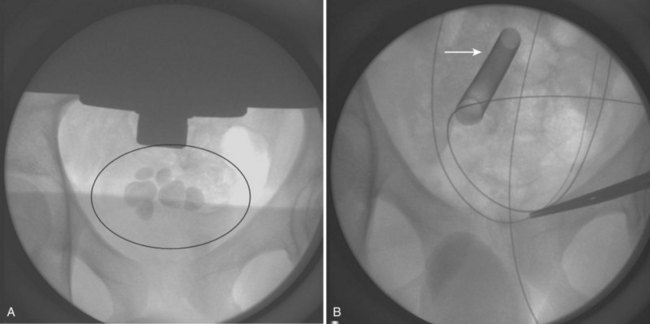

Having an updated and well-stocked system that is familiar to the operative staff is vital to efficient management. It usually falls on the nursing staff to care for the delicate instruments and keep up on repairs so that the instruments are operational when needed; maintenance is often needed after 20 to 30 uses. A “basic” ureteroscopic kit is listed below; however, variation exists based on the manufacturer. An array of semirigid and flexible pediatric ureteroscopes, in additional to ureteral access sheaths, is available from numerous companies (Buscarini and Conlin, 2008). In general, semirigid ureteroscopes usually have a 2.4- to 3.5-Fr working port and flexible ureteroscopes a 1.8- to 3.5-Fr working port. With flexible ureteroscopes, distal tip deflection up to 270 degrees can facilitate access to most lower pole stones (Figs. 135-2 and 135-3). However, smaller working areas and difficulties in exchanging instruments through the working element of a deflected ureteroscope may limit this treatment modality in some cases (Fig. 135–4).

Figure 135–4 A, A 7-year-old boy with two separate 7- to 9-mm stones within lower pole calices (left arrow). A ureteroscopic approach was attempted, but a lower pole infundibular–ureteropelvic junction angle greater than 270 degrees (right arrow) limited ureteroscopic access and visibility. B, A percutaneous nephrolithotomy was subsequently performed, clearing all stones in one sitting.